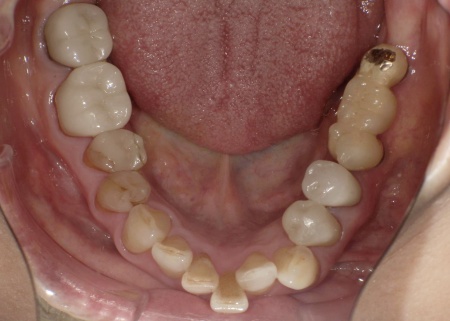

70代女性 歯根が折れた歯を抜いて金属バネを使用しない部分入れ歯で補った症例

拝見したところ、左上の歯(第2小臼歯)が欠損しており、この部分を補うために、両隣の歯を土台として橋を渡すように連結した被せ物「ブリッジ」が装着されていました。

レントゲン撮影をして詳しく検査した結果、ブリッジを支えている左上の歯(第1小臼歯)は、歯根が割れていることが判明しました。

このまま放置すると、周囲の骨や歯茎に炎症が広がるおそれがあります。また、歯の状態から温存は困難だと判断しました。

以上のことから、歯根が折れた歯を抜いたうえで、欠損部位を補う治療が必要だと診断しました。

第1小臼歯に歯根破折を認めました。